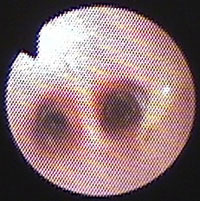

気管支鏡検査:第7病日に行った。肉眼所見で、左右主気管支内に白色円柱状物が多数みられた(図2)。ブラシ擦過細胞診にて、気管支粘膜上皮細胞、好酸球、杯細胞がみられた(図3)。気管支肺胞洗浄液(BAL)[RB2, 10ml×3, 回収率90%]にて総細胞数の軽度増加(421/μl)、好酸球数の増加(26.75%)がみられた。BAL液の培養にて細菌も真菌も検出されなかった。

図2 症例1の気管支鏡検査所見。左右主気管支内に白色円柱状物が多数みられた。